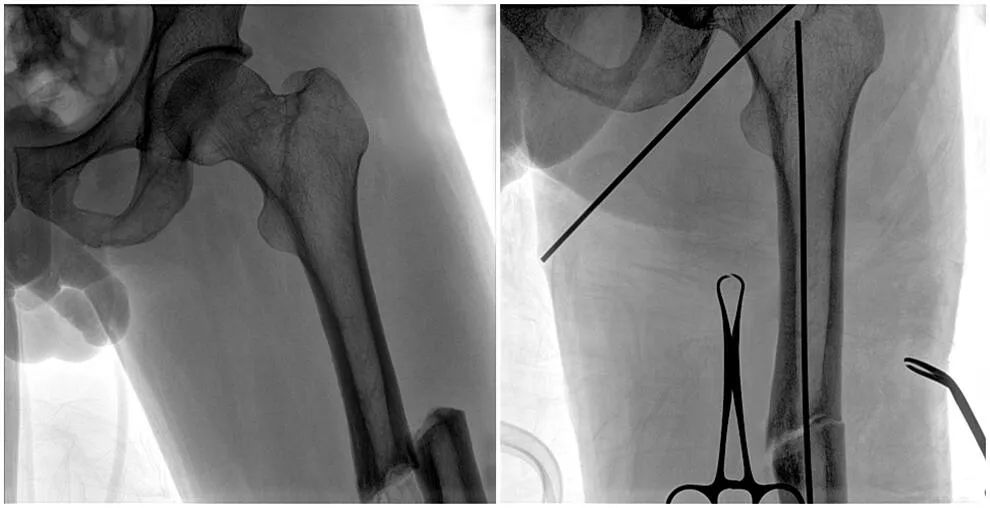

C形臂輔助手術過程

術中使用普愛醫療大平板一體式C形臂進行透視,判斷骨折情況及克氏針、髓內釘等金屬植入物的位置,進行調整。C形臂準確的術中定位,大大縮短了手術的時間,減輕了患者的痛苦,輔助手術順利完成。

在進行髓內釘內固定術時,醫生需要同時觀察到入釘點和骨折部位的情況,普愛醫療大平板一體式C形臂采用30CM×30CM的平板探測器,能夠呈現更廣闊的成像面積,滿足大部分長骨髓內釘內固定術的攝片需求。